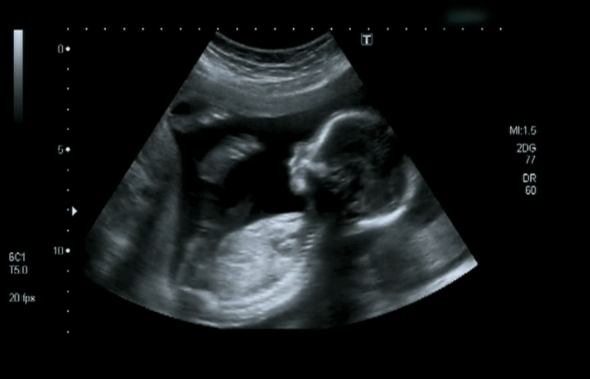

There are many reasons why one would require an abdominal ultrasound. One of the most popular reasons is for pregnancy. There are ultrasound systems that are specifically engineered and designed for this purpose including the GE Voluson (both portable and stationary options available) series. The Mindray DC-70 and the Samsung WS80A are other high quality systems that specialize in OB-GYN ultrasounds. Many of these systems are even capable of producing 3D and Live 3D images of the baby to trace and track it’s development.

Other reasons, as mentioned above, include check-ups on one’s liver and kidney. Spotting kidney stones, hernias, identifying tumors and gallstones are just a few other reasons for abdominal ultrasounds. These images can confirm regularities, illnesses, structural damages, growths and clots.